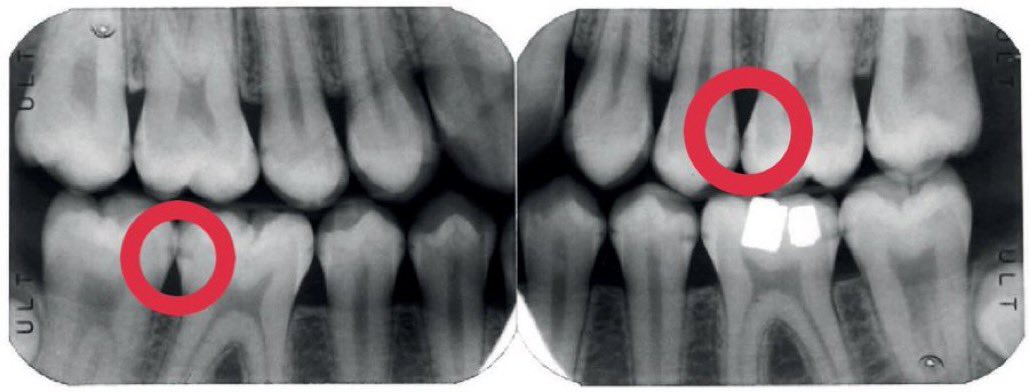

هذه التسوسات عادة تحدث اذا لم تستخدم الخيط السني بإنتظام..وهذا النوع "الخفي" من التسوس يحتاج اكتشاف مبكر عن طريق أشعة من نوع خاص(الصورة ١)وتعمل هذه الأشعة عادة كل ٦ أشهر خلال الفحص الدوري.. الصورة ٢: مقطع عرضي لتسوس مايين الأسنان

٤/الاشعة الصغيرة:

هذا ما تكشف عنه اشعة الأسنان الصغيرة: التسوسات في الأسطح الملساء او الأسطح ما بين الأسنان والتي لا يمكن كشفها بالعين خلال الفحص.. خاصة اذا كانت اسنانك متلاصقة (الطبيعي) يجب عمل هذه الأشعة خلال الكشف الدوري وكل ٦ اشهر

يمكن تقسيم التسوس للإنسان العادي بتسوس ظاهر أو تسوس بين الأسنان. الاول تراه بعينك حين تنظر في المرآة، والثاني لا يمكن اكتشافه بدون أشعة خاصة وهامة يعملها الطبيب خلال التشخيص والفحص الدوري